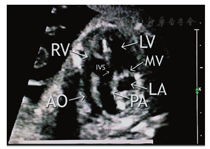

孕妇,27岁,孕1产0,孕25周。行产前超声检查示:胎儿如孕25+4周,腹部横切面显示腹主动脉与下腔静脉位置排列关系正常,腹腔脏器正位;四腔心切面显示心尖指向左侧,房室大小正常;心室流出道切面显示升主动脉(内径3.3 mm)及肺动脉大部分(内径6.7 mm)发自右心室,比例(PA/AO)为2.03,两者起始部呈平行排列,室间隔上部中断4.9 mm,肺动脉骑跨于室间隔上;彩色多普勒示左心室血流经过室间隔缺损直接射入肺动脉内(图1,图2);三血管及三血管气管切面显示主动脉位于肺动脉右前方,与动脉导管共同形成"V"形血管结构消失,多切面检查主动脉弓于左锁骨下动脉以下未能与降主动脉连续,无法显示完整的主动脉弓长轴切面(图3)。超声诊断:胎儿心脏发育异常,右心室双出口(Taussig-Bing型)、室间隔缺损、升主动脉发育不良、主动脉弓离断(A型)可能性大。胎儿引产后,心脏解剖证实超声诊断(图4)。